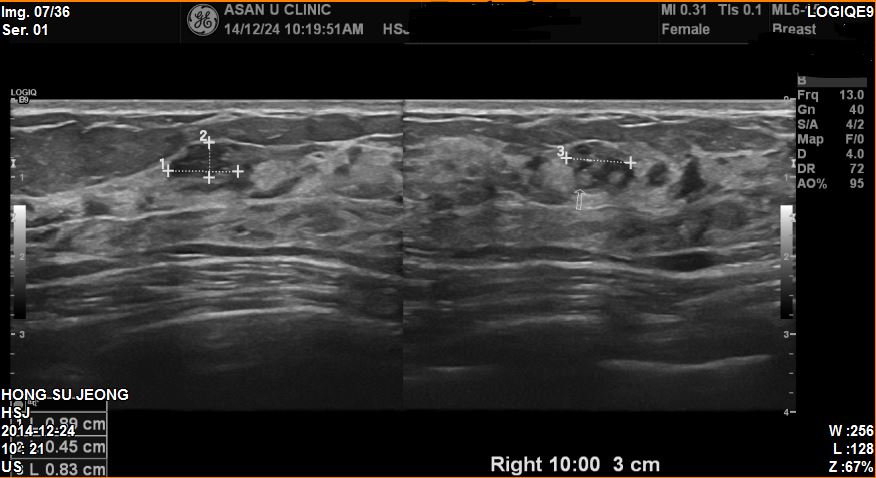

양측유방통으로 내원하신 41세 환자분이십니다

본원초음파 후  우측 10방향 유두에서 3cm 떨어진곳에 0.9cm혹을

조직검사하였고  결과상 상피내암진단되었습니다.